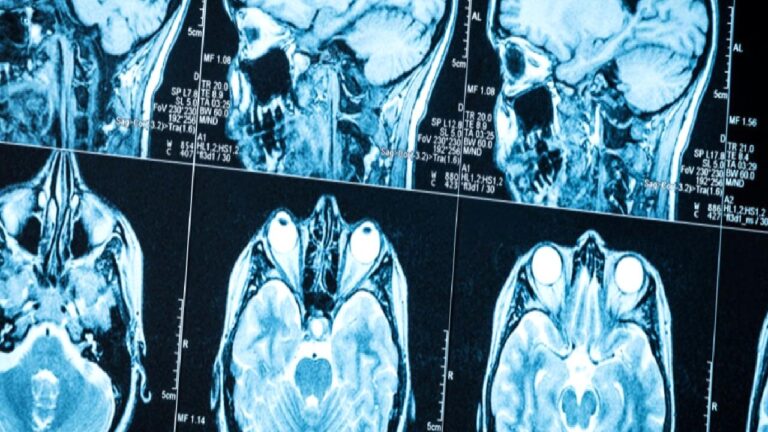

Tıpta yapay zekanın potansiyeli her geçen gün daha fazla somutlaşıyor. Hollanda Kanser Enstitüsü ile Robovision Healthcare’in ortak yürüttüğü yeni bir araştırma, yapay zekanın beyin MRI taramalarında şimdiye kadar kolaylıkla gözden kaçabilen küçük tümörleri yüksek doğrulukla tespit edebildiğini ortaya koydu.

Bu gelişmenin önemini artıran detaylardan biri, söz konusu tümörlerin sıklığı. Beyin metastazları, merkezi sinir sisteminde en yaygın görülen tümör türlerinden biri olarak biliniyor. Robovision’un verilerine göre bu tür tümörler, yetişkin kanser hastalarının yaklaşık %17’sinde ortaya çıkabiliyor. Ancak erken aşamada tespit edilmeleri oldukça zor. Tümörler genellikle 3 milimetreden küçük boyutlarda oluşuyor ve hızlı bir şekilde büyüyebiliyor. Tek bir MRI taramasında elde edilen yüzlerce görüntü arasında bu boyuttaki lezyonları fark etmek, insan gözü için her zaman mümkün olmuyor.

Ancak Radiology dergisinde yayımlanan çalışmaya göre, yapay zekayla bu zorluk aşılmak üzere. Robovision Healthcare tarafından geliştirilen BrainMets.ai adlı yapay zeka sistemi, MRI görüntülerinde küçük lezyonları dahi yüksek doğrulukla tanıyabiliyor. Sistemin lezyon düzeyindeki genel duyarlılığı %97,4 olarak açıklandı. Başarı oranı, tümörlerin boyutuna göre farklılık gösterse de sonuçlar genel olarak oldukça etkileyici.